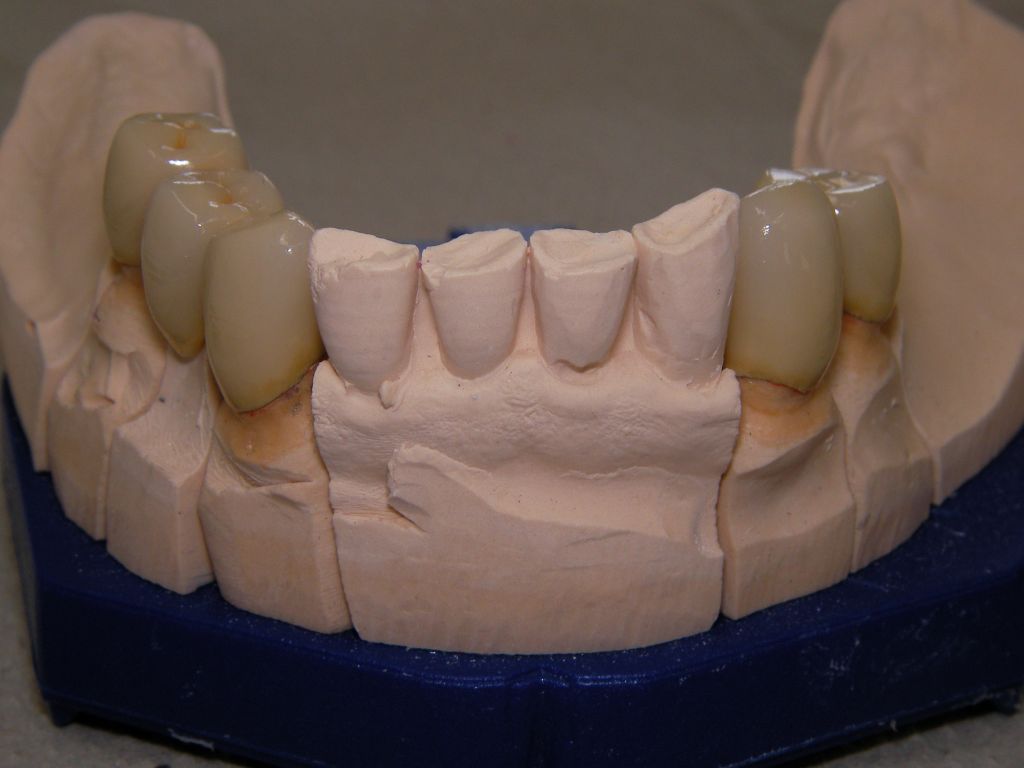

Das Hauptproblem dieses Falles lag im Oberkiefer - die über die Jahrzehnte abgeknirschten, kurzen Zähne erschweren Kronen, die durch eine Prothese belastet werden können. Die gewählte Lösung besteht darin, die Zähne nur rundherum zu beschleifen, aber nicht mehr zu kürzen und die Prothese mit einem Druckknopfsystem an die Zähne anzukoppeln, das ein "Spiel" aufweist, so daß die Prothese nicht als Hebelarm auf die schwachen Restzähne wirken kann. Rechts die beschliffenen Zähne kurz vorm Zementieren der Kronen.

Oberkiefer vorm Zementieren

Oberkiefer von innen